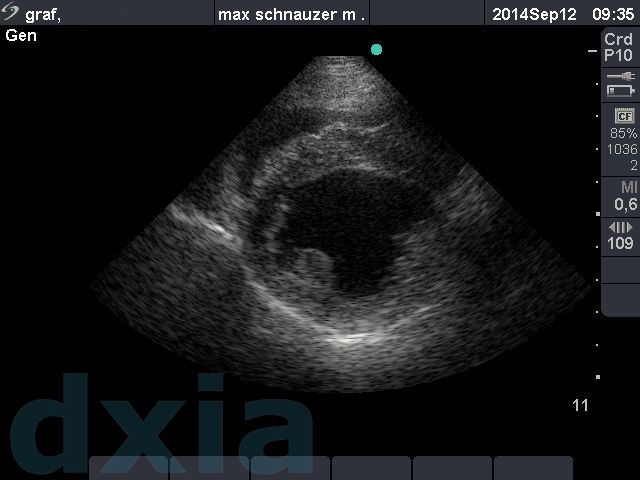

Imágenes obtenidas durante el estudio ecocardiográfico

Eje corto max

Eje corto derecho

No aplastamiento del septo IV. Contracción conservada. Base cardíaca. No dilatación de aurícula izquierda.